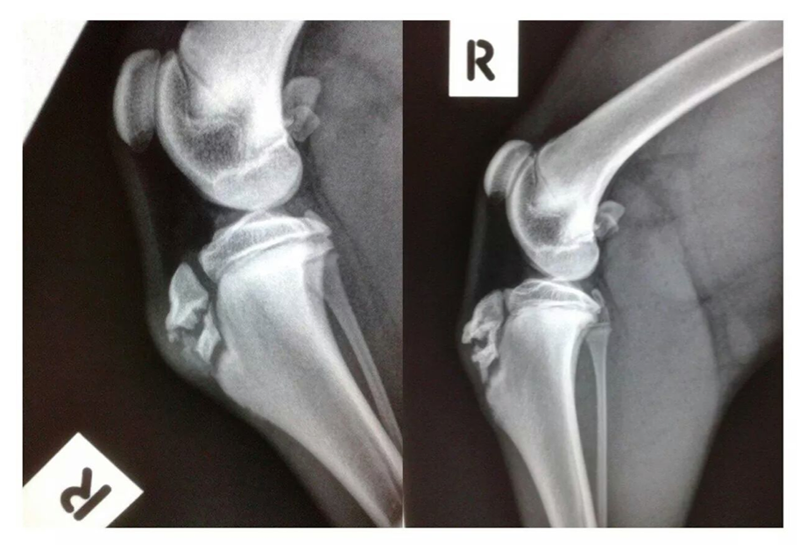

Please look below at all these x-rays from last years random friend’s injuries ( and these are without even searching as these happen all the time). If it is not a growth plate , it is a neck, back, wrist, hock, ribs or any large bones for that matter. One of the most common example is when a small piece of the knee joint splits, which end up in a 2-3000€ surgery. I do not see much point in taking such a huge risk, so don’t run adults and pups! Period!

Here is the proof! More info after the pictures!

• The diagrams below show the different type of fractures (the blue line represents the soft growth plate tissue, the red line represents the fracture line, and the speckled red line is a crushed growth plate).

Common locations of the various Salter-Harris growth plate fractures in dogs and cats • Type1 – hip joint (slipped femoral capitis), knee (distal femur)

• Type 2 – knee (distal femur)

• Type 3 – elbow (distal humerus)

• Type 4 – elbow (distal humerus)

• Type 5 – 1. wrist or carpus (distal ulna or the distal radius less commonly), this results in an angular limb deformity); 2. ankle or hock (distal tibia)